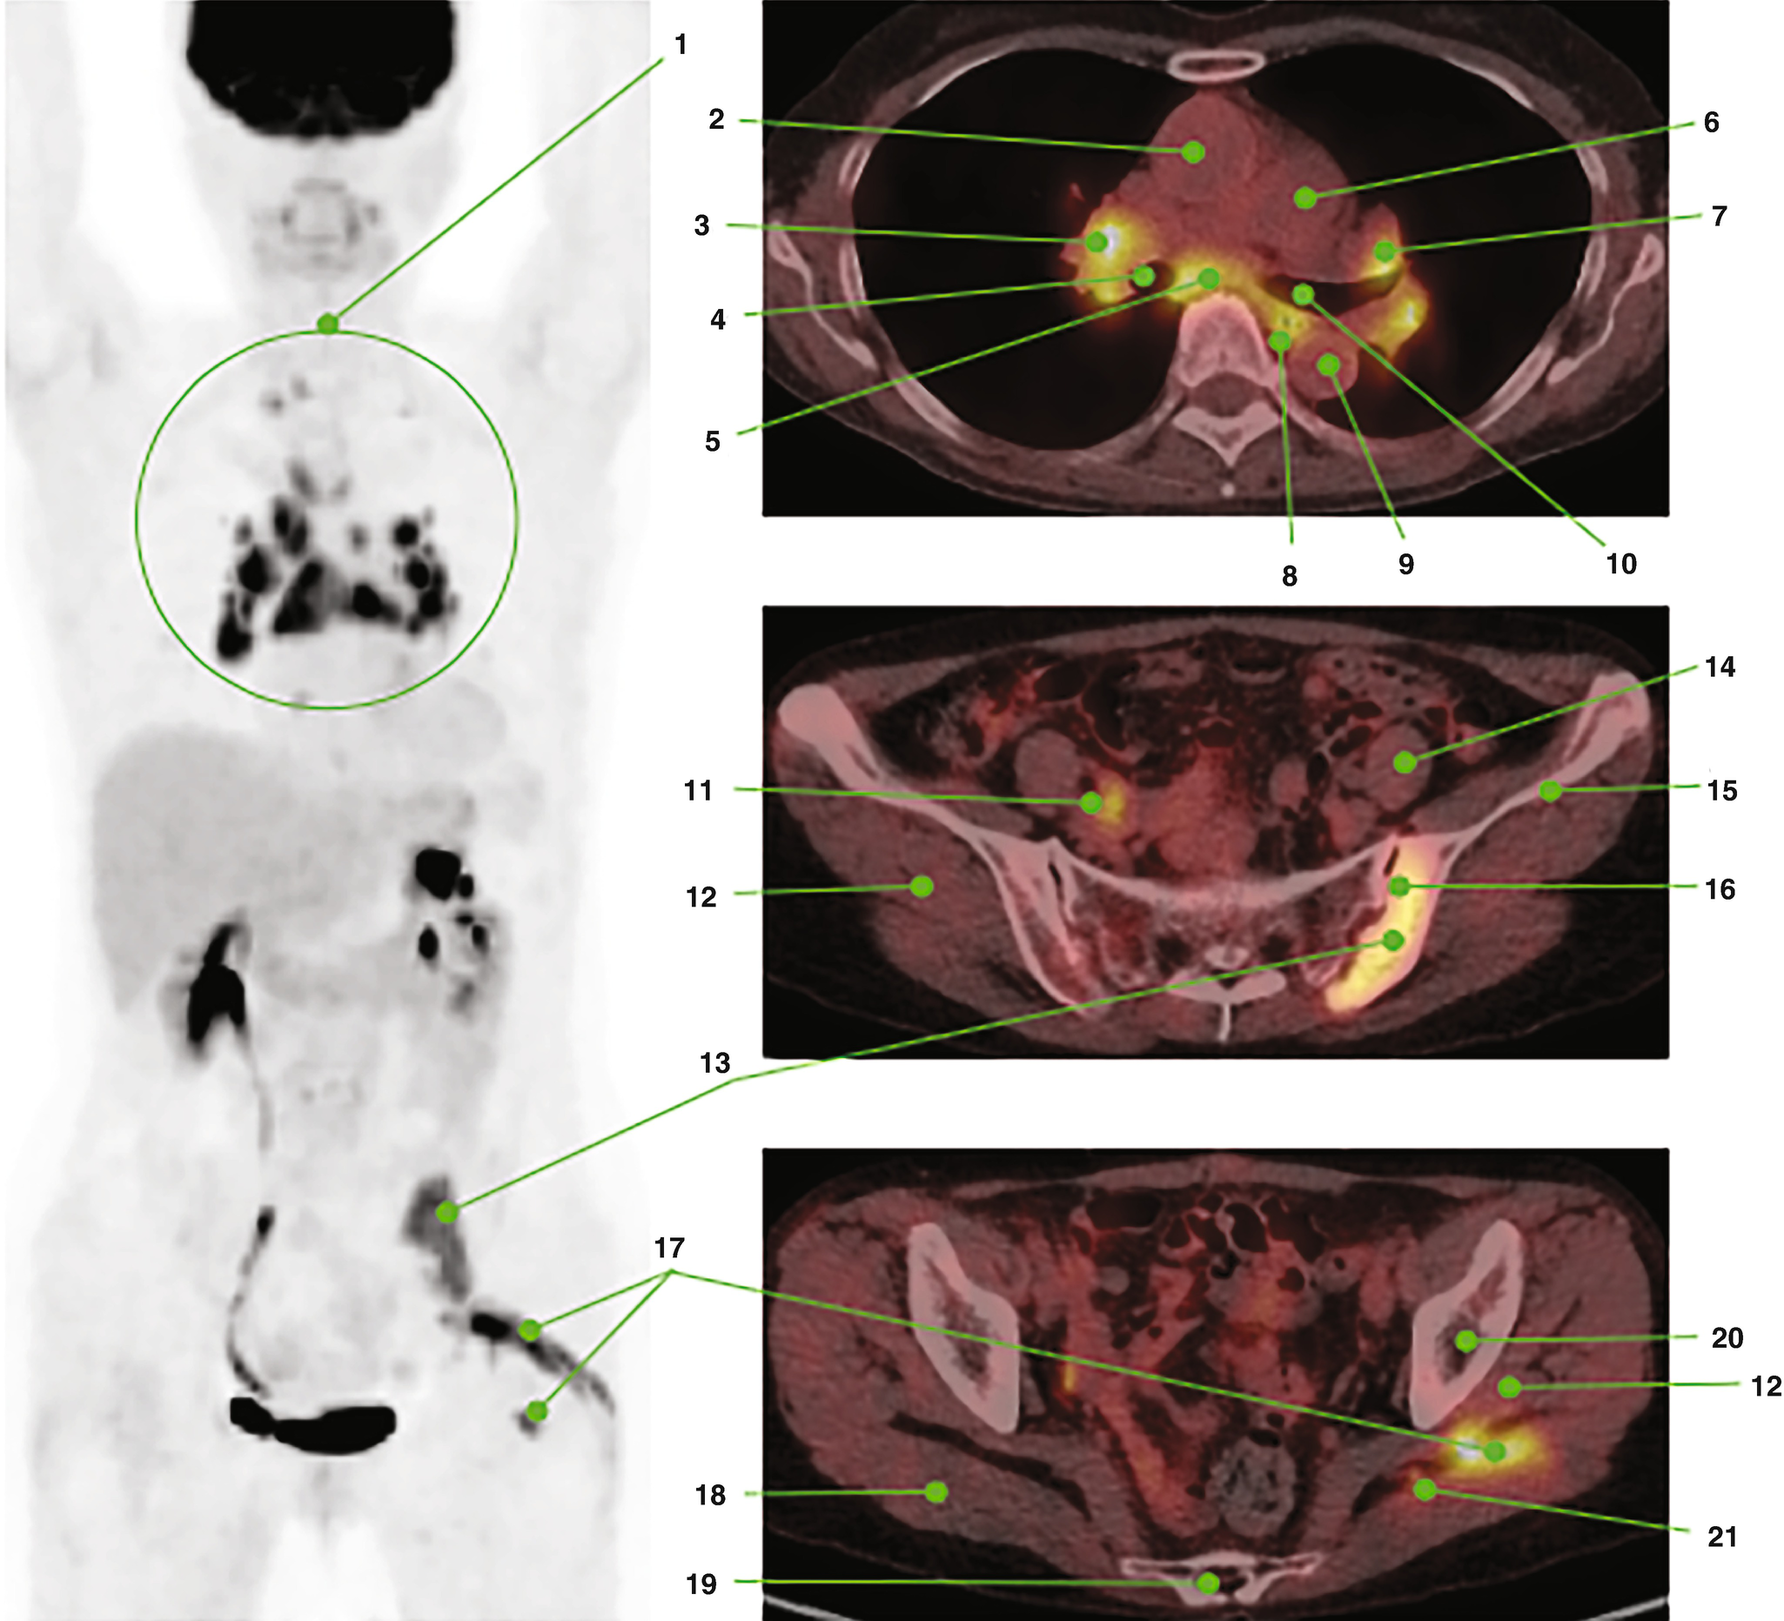

Facilitate learning with our scientific Pet/ct Lymphatic System gallery of hundreds of educational images. accurately representing photography, images, and pictures. perfect for research publications and studies. Browse our premium Pet/ct Lymphatic System gallery featuring professionally curated photographs. Suitable for various applications including web design, social media, personal projects, and digital content creation All Pet/ct Lymphatic System images are available in high resolution with professional-grade quality, optimized for both digital and print applications, and include comprehensive metadata for easy organization and usage. Explore the versatility of our Pet/ct Lymphatic System collection for various creative and professional projects. Multiple resolution options ensure optimal performance across different platforms and applications. Whether for commercial projects or personal use, our Pet/ct Lymphatic System collection delivers consistent excellence. Professional licensing options accommodate both commercial and educational usage requirements. Each image in our Pet/ct Lymphatic System gallery undergoes rigorous quality assessment before inclusion. Time-saving browsing features help users locate ideal Pet/ct Lymphatic System images quickly. Advanced search capabilities make finding the perfect Pet/ct Lymphatic System image effortless and efficient. Comprehensive tagging systems facilitate quick discovery of relevant Pet/ct Lymphatic System content. Instant download capabilities enable immediate access to chosen Pet/ct Lymphatic System images.